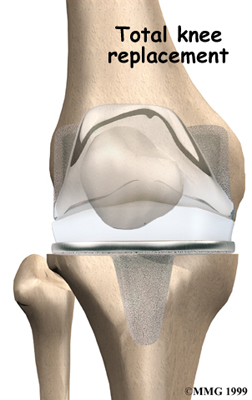

Artificial Knee Replacement

An artificial knee replacement is the ultimate solution for advanced knee OA.

Surgeons prefer not to put a new knee joint in patients younger than 60. This is because younger patients are generally more active and might put too much stress on the joint, causing it to loosen or even crack. A revision surgery to replace a damaged prosthesis is harder to do, has more possible complications, and is usually less successful than a first-time joint replacement surgery.

Related Document: FYZICAL West Pearland's Guide to Artificial Joint Replacement of the Knee